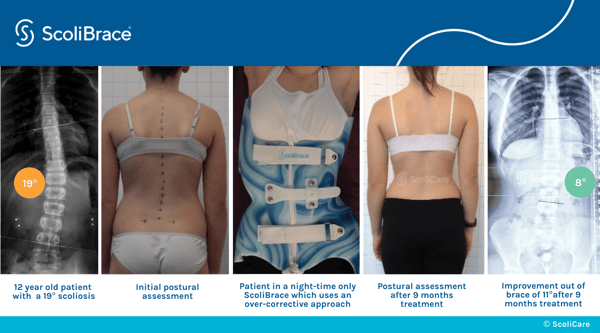

How ScoliBrace Works

A precise, over-corrective approach that realigns your spine.

ScoliBrace gently guides the spine and body into the opposite posture of the scoliosis curve, helping realign it over time through consistent, targeted correction.

The Results You Can Expect

Visible improvements. Real relief.

Functional freedom.

ScoliBrace delivers more than just cosmetic changes — it enhances posture, reduces pain, and boosts comfort in daily life.

- Progressive reduction in spinal curvature

- Better symmetry: shoulders, waist, and rib cage

- Less discomfort during everyday movement

Achievable & Measurable Results

Real progress you can see and feel.

Our goal is clear: reduce curves, enhance posture, and improve comfort within a 24-month care window.

- Trackable curve reduction over time

- Visible body alignment and posture improvement

- Routine check-ins for tailored progress

See the Results for Yourself

Real patients. Visible progress. Explore our success stories and before & after transformations that showcase the power of consistent chiropractic care and scoliosis bracing.